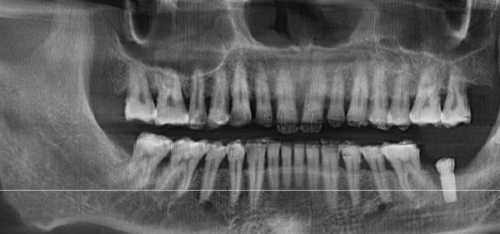

2. 种植牙:依据品牌与材料选择,价格从4599元 - 17000元都有。